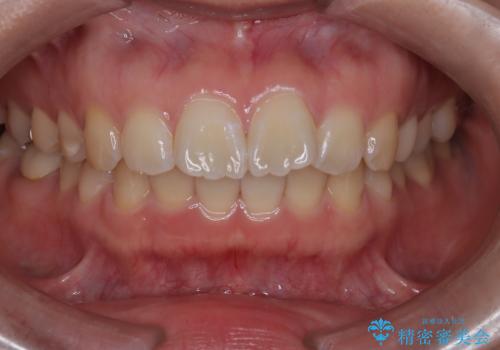

目立たない矯正で口元の突出感を解消

- 口元が出ている(突出している)ことを気にされて来院されました。精密な検査の結果、前歯を大きく後退させるスペースが必要と診断。患者様の**「前歯を下げたい」という強いご要望に応えるため、上下左右の第一小臼歯を抜歯し、そのスペースを利用して前歯を奥へ移動させる治療計画を立案しました。また、人目を気にせず治療できるよう、上顎に裏側矯正、下顎に表側矯正を組み合わせたハーフリンガル矯正**を提案しました。

今回の矯正治療では、前歯を大きく後退させるスペースを確保するため、計画通り上下左右の第一小臼歯を抜歯しました。装置には、上顎には目立たない裏側矯正(舌側矯正)を、下顎には透明な審美ブラケットを使用するハーフリンガル矯正を採用しました。抜歯によってできたスペースを最大限に活用し、前歯を効率よく後方へ移動。治療の結果、口元の突出感が大幅に解消され、Eライン(横顔の美しさの基準)も改善しました。人目を気にすることなく治療を完遂し、自信の持てる美しい横顔を獲得していただけました。